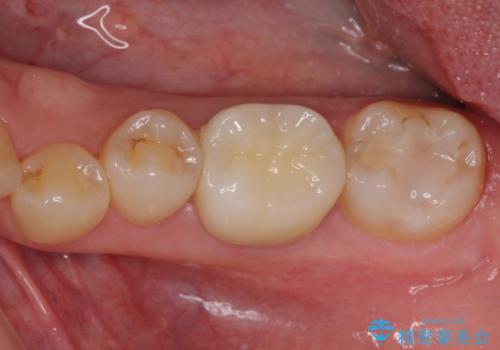

処置開始前から神経組織を部分的に除去する可能性が高いことが分かっていたため、ラバーダムなどの環境を整え、無菌的環境下にて処置を進めて行きました。

虫歯は深くまで進行しており、歯冠部後方の神経から出血が認められました。炎症を起こしている神経を除去したところ出血が治まったので、生体親和性の非常に高いセメントにて充填し、仮封をし、その日のうちに仮歯を装着しました。

後日状態を確認したところ、残された神経に異常がなかったため、フルジルコニアクラウンにて補綴治療を行いました。